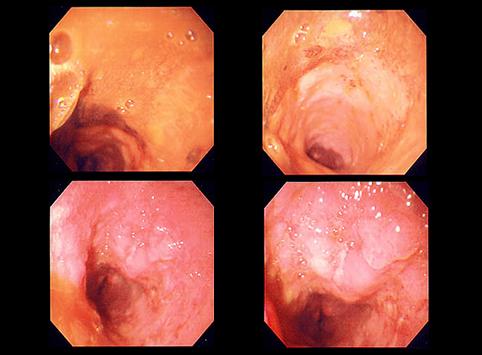

질환(병리주체)의 분류 악성 상피성종양/편평상피암

부위(장기별) 식도/2개 이상

검사방법 내시경

종양의 육안분류 5형(분류불능)/

종양의 최대경(밀리미터) 40이상

종양의 심달도 mp